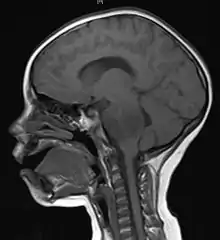

Imaging

Medical imaging plays a central role in the diagnosis of brain tumors. Early imaging methods – invasive and sometimes dangerous – such as pneumoencephalography and cerebral angiography have been abandoned in favor of non-invasive, high-resolution techniques, especially magnetic resonance imaging (MRI) and computed tomography (CT) scans, though MRI is typically the reference standard used.[37] Neoplasms will often show as differently colored masses (also referred to as processes) in CT or MRI results.

- Benign brain tumors often show up as hypodense (darker than brain tissue) mass lesions on CT scans. On MRI, they appear either hypodense or isointense (same intensity as brain tissue) on T1-weighted scans, or hyperintense (brighter than brain tissue) on T2-weighted MRI, although the appearance is variable.

- Contrast agent uptake, sometimes in characteristic patterns, can be demonstrated on either CT or MRI scans in most malignant primary and metastatic brain tumors.

- Pressure areas where the brain tissue has been compressed by a tumor also appear hyperintense on T2-weighted scans and might indicate the presence a diffuse neoplasm due to an unclear outline. Swelling around the tumor known as peritumoral edema can also show a similar result.

This is because these tumors disrupt the normal functioning of the BBB and lead to an increase in its permeability. More recently, advancements have been made to increase the utility of MRI in providing physiological data that can help to inform diagnosis and prognosis. Perfusion Weighted Imaging (PWI) and Diffusion Weighted Imaging (DWI) are two MRI techniques that reviews have been shown to be useful in classifying tumors by grade, which was not previously viable using only structural imaging.[38] However, these techniques cannot alone diagnose high- versus low-grade gliomas, and thus the definitive diagnosis of brain tumor should only be confirmed by histological examination of tumor tissue samples obtained either by means of brain biopsy or open surgery. The histological examination is essential for determining the appropriate treatment and the correct prognosis. This examination, performed by a pathologist, typically has three stages: interoperative examination of fresh tissue, preliminary microscopic examination of prepared tissues, and follow-up examination of prepared tissues after immunohistochemical staining or genetic analysis.